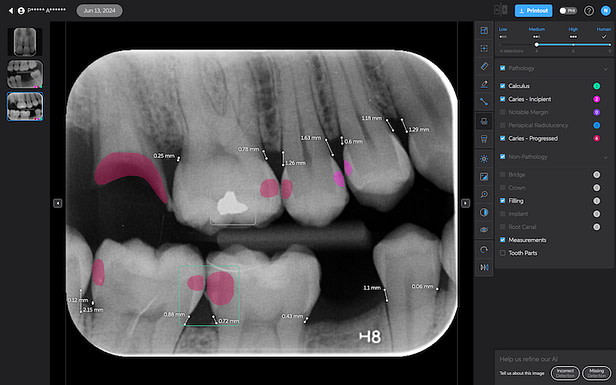

The system uses two shades of pink to indicate potential caries:

- Light pink: Incipient caries (100% in enamel) - we will often review

- Darker magenta: Caries extending into dentin - we need to restore

The system even provides a percentage breakdown of enamel vs. dentin involvement. I have been blown away by its accuracy while using it, and it makes something that feels quite subjective (reading shades of grey) into a science.

This feature is very useful for patient education and deciding between preventive measures and restorative treatment. However, remember that radiographic evidence alone is not always sufficient for a definitive caries diagnosis.